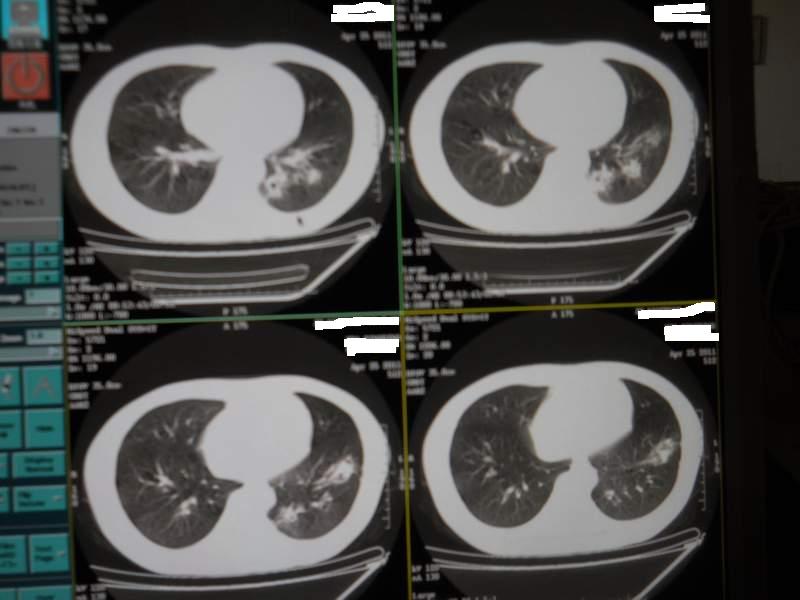

肺霉菌感染

男,22岁,一年前诊断马尔菲尼青霉菌感染,多次复查CT。多次HIV阴性。最近两次CT图片。有实验室结果。

最近实验室检查结果:霉菌感染。